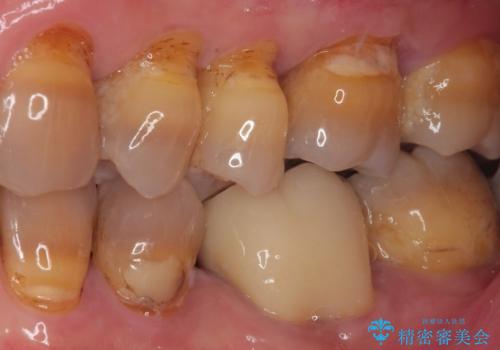

- 上顎大臼歯が食事の度に痛みを感じるとのことで来院された患者様です。

レントゲン写真などで診査を行ったところ、神経組織が壊死し、根尖部周辺の骨に炎症が認められました。

まずは根管治療を行い、症状が消退したことを確認してオールセラミッククラウンにて補綴治療を行うこととしました。